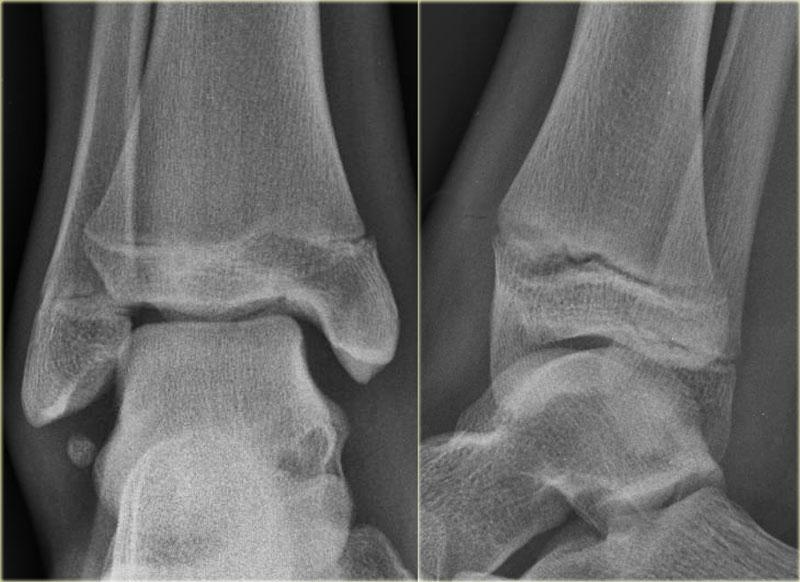

Các hình ảnh cho thấy một trường hợp gãy Weber B rõ ràng.

Trên tư thế thẳng (AP), đường thấu quang dạng tuyến tính là dấu hiệu gợi ý gãy tertius (mũi tên đỏ).

Dấu hiệu này xuất hiện do sự lệch trục nhẹ của mảnh gãy.

Tương tự, trong một số trường hợp, sự lệch trục có thể tạo ra một đường tăng tỷ trọng dạng tuyến tính.

Trong trường hợp này, có gãy Weber B kèm theo bong điểm bám mắt cá trong.

Đường tăng tỷ trọng trên tư thế thẳng (AP) gợi ý một mảnh gãy tertius lớn.

Gãy tertius này cũng có thể thấy trên tư thế nghiêng, nhưng trong nhiều trường hợp chúng ta cần kết hợp thông tin từ cả hai tư thế nghiêng và thẳng để chẩn đoán gãy tertius.